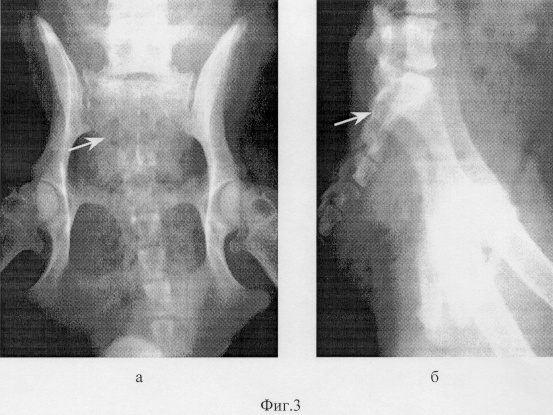

Фиг.1 – рентгенограмма таза животного до лечения: а – прямая, б – боковая проекции;

Собака, возраст 2 года, самка, диагноз: закрытый изолированный поперечный перелом крестца на уровне второго сегмента (фиг.1).